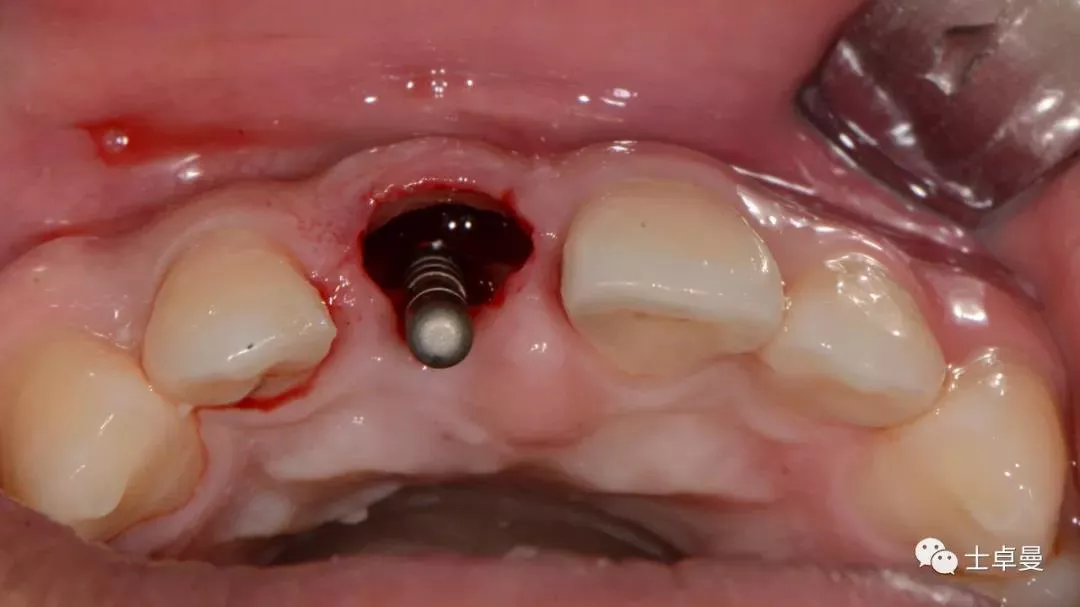

· 分根拔除11后,保留唇侧牙根盾片;

· 逐级扩孔后行种植体植入术;

· 植入Straumann® Roxolid® SLActive® BLT 4.1mm×16mm种植体,扭力15Ncm;

分根

拔出腭侧牙根

保留唇侧牙片

牙周探针探查牙片位置及松动度